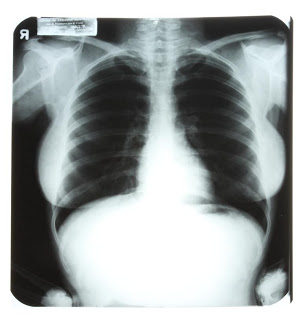

MARILYN MONROE CHEST X-RAY

Winning bid $20,000.00

Estimate: $800.00 – $1,200.00

Starting: $400.00

Description: X-ray of Marilyn Monroe’s chest. Printed on the x-ray is the following information, “Cedars of Lebanon Hospital/Drs. E. Freedman and S. Finck/ Name Di Maggio Marilyn/ No. 50612 Date 11-10-54/ Ref. By Dr. L. Krohn.” As a radiology resident at Cedars, a young doctor obtained these x-rays. When he taught at the school himself, he used these x-rays to ensure that students were paying attention. Monroe was said to have known about the x-rays and their use, about which she said “Isn’t that sweet.” Monroe’s hospital visit was said to be for her chronic endometriosis – or as her doctor’s described it, “For correction of a female disorder she has suffered for years.” Accompanied by a copy of the X-Ray. 17 by 13 3/4 inches